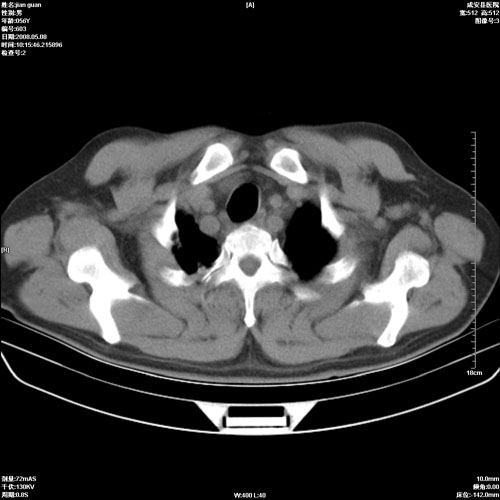

病人 男 60岁 主诉 胸闷 无明显发热 一般情况尚可。

两上肺陈旧性结核;慢支肺气肿、伴感染?

两上肺陈旧性结核;慢支肺气肿

1.两上肺陈旧性结核;慢支肺气肿。

陈旧性肺结核

两上肺陈旧性结核,慢支肺气肿。

两上肺陈旧性结核;慢支肺气肿。肺肺间质纤维化

两上肺陈旧性结核;慢支肺气肿。